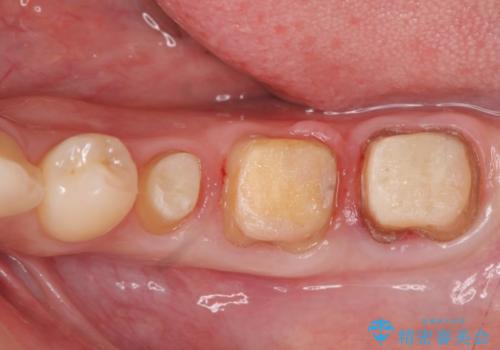

- 治療途中で放置してしまった歯の治療の再開を希望され来院されました。

虫歯を除去すると、歯ぐきよりも深い虫歯であることが判明したため歯周外科を行い問題を解決していきます。

セラミック治療の注意事項(リスク・副作用など)

- 天然歯を削ります

- 硬い素材は天然歯を傷つけてしまう場合があります

- かみ合わせや歯ぎしりが強すぎる方はセラミックが割れてしまう可能性があります

- 自費診療(保険適用外治療)となります